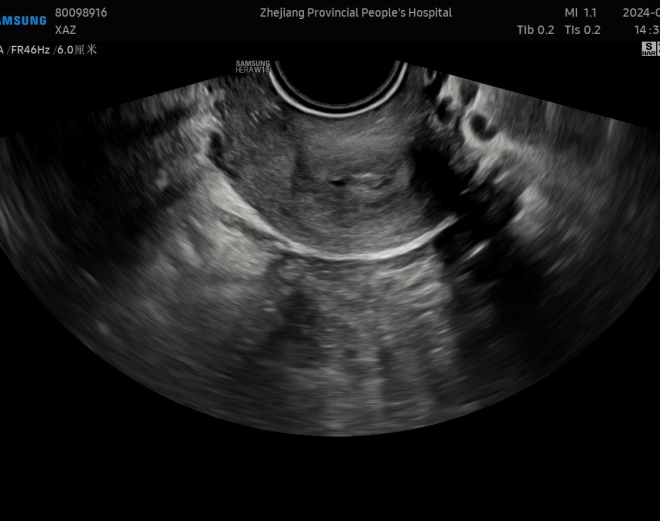

地屈孕酮20mg qd po每次月经第5天开始口服;术后第3个月:月经量少,无痛经,无明显副反应。复查阴道B超:子宫前位,切面大小正常,后壁肌层回声增粗,分布不均匀,内见多个条状回声,前峡部见0.9cm*0.7cm*0.9cm(宽径*长径*深径)无回声区。单层内膜厚度0.2cm,回声均匀,宫腔分离约0.5cm。提示:子宫后壁肌层回声改变,考虑术后改变;子宫前峡部暗区,憩室可能。CA125:14.1U/ml。阴道超声图如下: